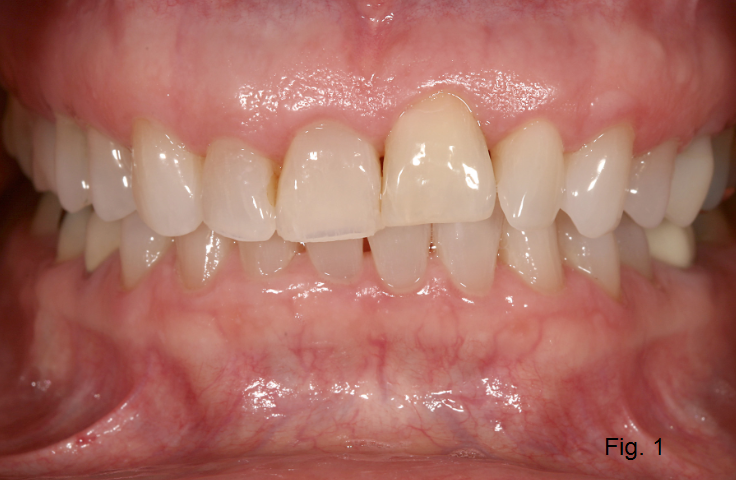

If, however, the tooth became ankylosed after growth was complete, there may be no impact on the hard and soft tissue positions. The patient in Figure 1 is in her late 50s and has tooth #9 ankylosed. Given the position of the gingival margin and incisal edge of this tooth compared with other teeth in the arch, it is apparent that it became an ankylosed tooth at some time prior to the completion of growth.